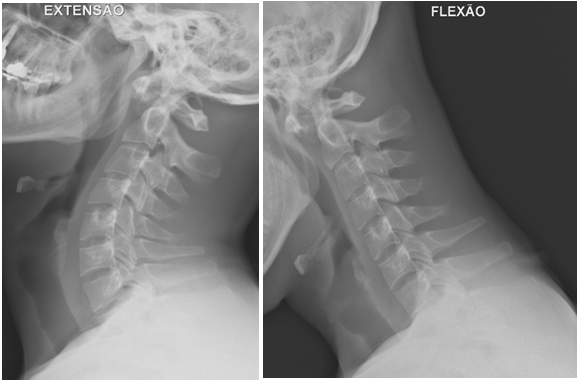

A 27-year-old male patient with no relevant medical or surgical history and working in the military army, was observed in an Orthopedics consultation, referred from primary health care for complaints of neck pain, without irradiation to the upper limbs, associated with limitation of mobility, especially in sagittal plane movements, with 4 months of evolution (Neck Disability Index (NDI) of 26). The patient denied a history of trauma, but reported upper respiratory infection (pharyngitis) one month before the onset of cervical pain. Physical examination revealed decreased cervical mobility, without other major findings. The diagnostic study began with two-plane cervical radiography (Figure 1), with an approximate ADI value of 10.5 mm, as well as dynamic radiographs (Figure 2), which demonstrated C1-C2 dynamic instability (ADI of 10.9 and 9.8 mm respectively). The CT study confirmed atlanto-axial sub dislocation and excluded the presence of fractures or facet subluxations (Figure 3). The study was complemented by magnetic resonance imaging, which confirmed atlanto-axial sub dislocation, associated with inflammation and thickening of the paravertebral soft tissues, with transverse ligament incompetence (Figure 4 - magnetic resonance imaging). Due to the decreased mobility of the upper cervical spine, the possibility of Meningitis was raised. Blood analytical study showed marginal elevation of C-Reactive Protein (28 mg/L), thus, the hypothesis of Grisel's Syndrome was placed. The patient was initially treated with the use of a Minerva cervical collar and broad-spectrum empirical antibiotic therapy with Ceftriaxone for 6 weeks, but after this period, there was unfavorable clinical evolution, with worsening of cervical pain and functional status (NDI of 30). Surgical treatment was therefore elected, through posterior atlanto-axial fixation, which is in accordance with other cases published in the literature.2The surgery was uneventful and the patient had a favorable clinical course, with significant improvement in neck pain and joint mobility, with an improvement in the NDI from 30 to 5. Radio graphically, a reduction in atlanto-axial subluxation was confirmed (Figure 5), which remained stable until 5 years of follow-up. There were no late complications and the patient resumed his normal activities.

Figure 2 Dynamic study with C1-C2 instability.